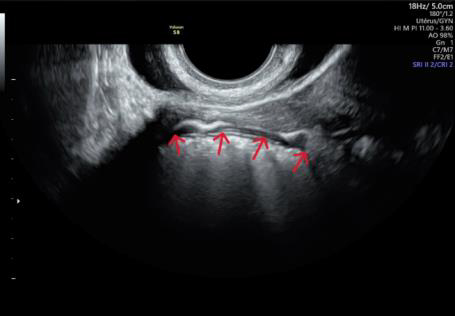

L’échographie pelvienne

pour évaluer votre réserve ovarienne, une échographie endo-vaginale sera réalisée en début de cycle (entre J2 et J6) et permettra de compter les follicules antraux et d’évaluer votre cavité utérine par une échographie 3D.